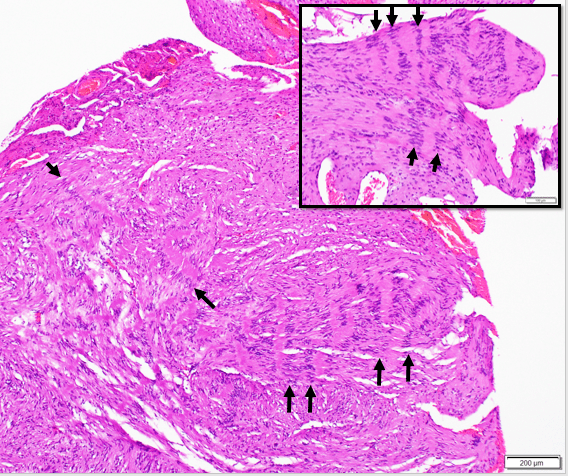

Schwannomas are peripheral nerve sheath tumors that arise from cells that myelinate peripheral nerve axons called Schwann cells. A classic histologic finding in schwannomas are Verocay bodies (arrows), which consist of short palisades of tumor cell nuclei separated by eosinophilic anucleate bands of tumor cell processes. Verocay bodies are often more prominent in schwannomas that arise in the setting of a familial tumor syndrome, such as Schwannomatosis. Though considered a classic histologic finding, Verocay bodies are not required to make a diagnosis of Schwannoma.